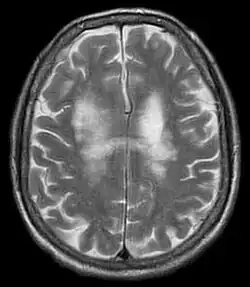

Eine relativ sichere Diagnose ist nur durch den Nachweis der JC-Virus-DNA im Liquor cerebrospinalis mittels Polymerasekettenreaktion (PCR) möglich. Der Nachweis des Virus im Urin lässt keinen Zusammenhang mit der Erkrankung zu, da etwa 20 % der Bevölkerung das Virus dauerhaft ausscheiden. Die relativ unspezifischen Demyelinisierungsherde, die mit einer Magnetresonanztomografie (MRT, Kernspintomografie) nachgewiesen werden können, können einen Beitrag zur Verdachtsdiagnose leisten. Die Herde stellen sich bei T1-Wichtung hypointens, in der T2- und Flair-Sequenz hyperintens dar und nehmen kein Kontrastmittel auf. Typisch sind flächig konfluierende und symmetrische Signalveränderungen unter Aussparung der Hirnrinde. Diese liegen oft parietal. Eine Differenzierung zu anderen Veränderungen gleichen Aussehens (zum Beispiel bei der Multipler Sklerose (MS) oder dem Posterioren reversiblen Enzephalopathiesyndrom (PRES)) ist ohne Krankengeschichte aufgrund der MRT-Befunde allein nicht möglich. Das Virus kann auch elektronenmikroskopisch in Hirngewebe nachgewiesen werden.